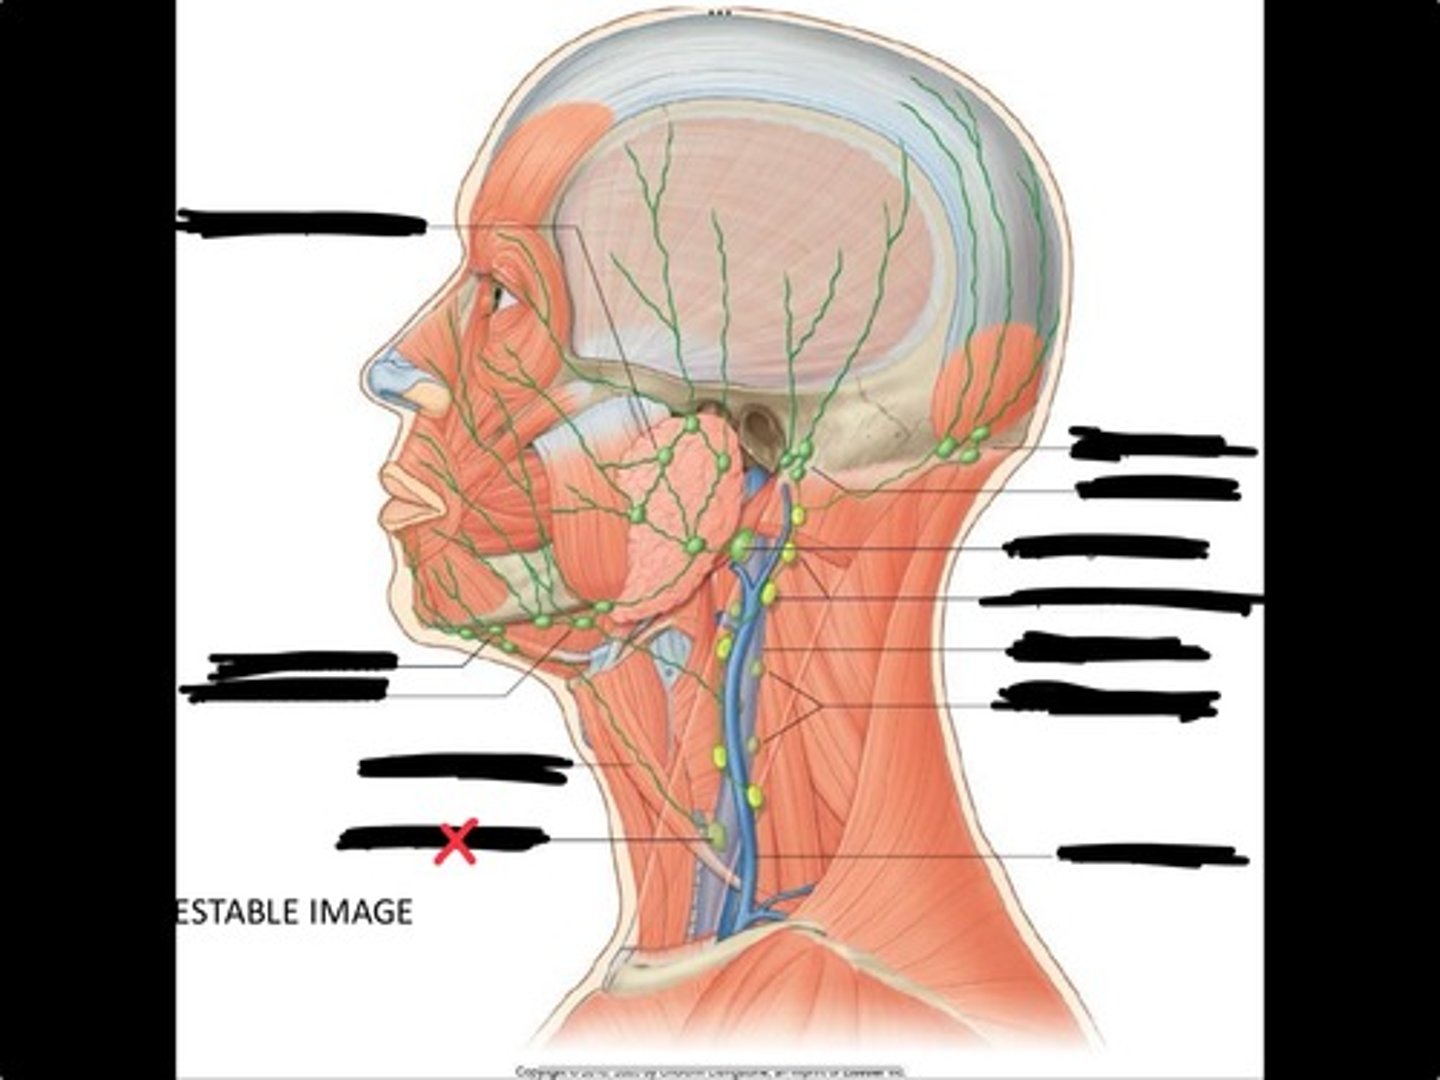

Jugulo-omohyoid node

Omohyoid muscle

Submandibular nodes

Submental nodes

Pre-articular/parotid nodes

Occipital nodes

Mastoid nodes

Jugulodigastric nodes

Superficial cervical nodes

Internal jugular vein

Deep cervical nodes

External jugular vein